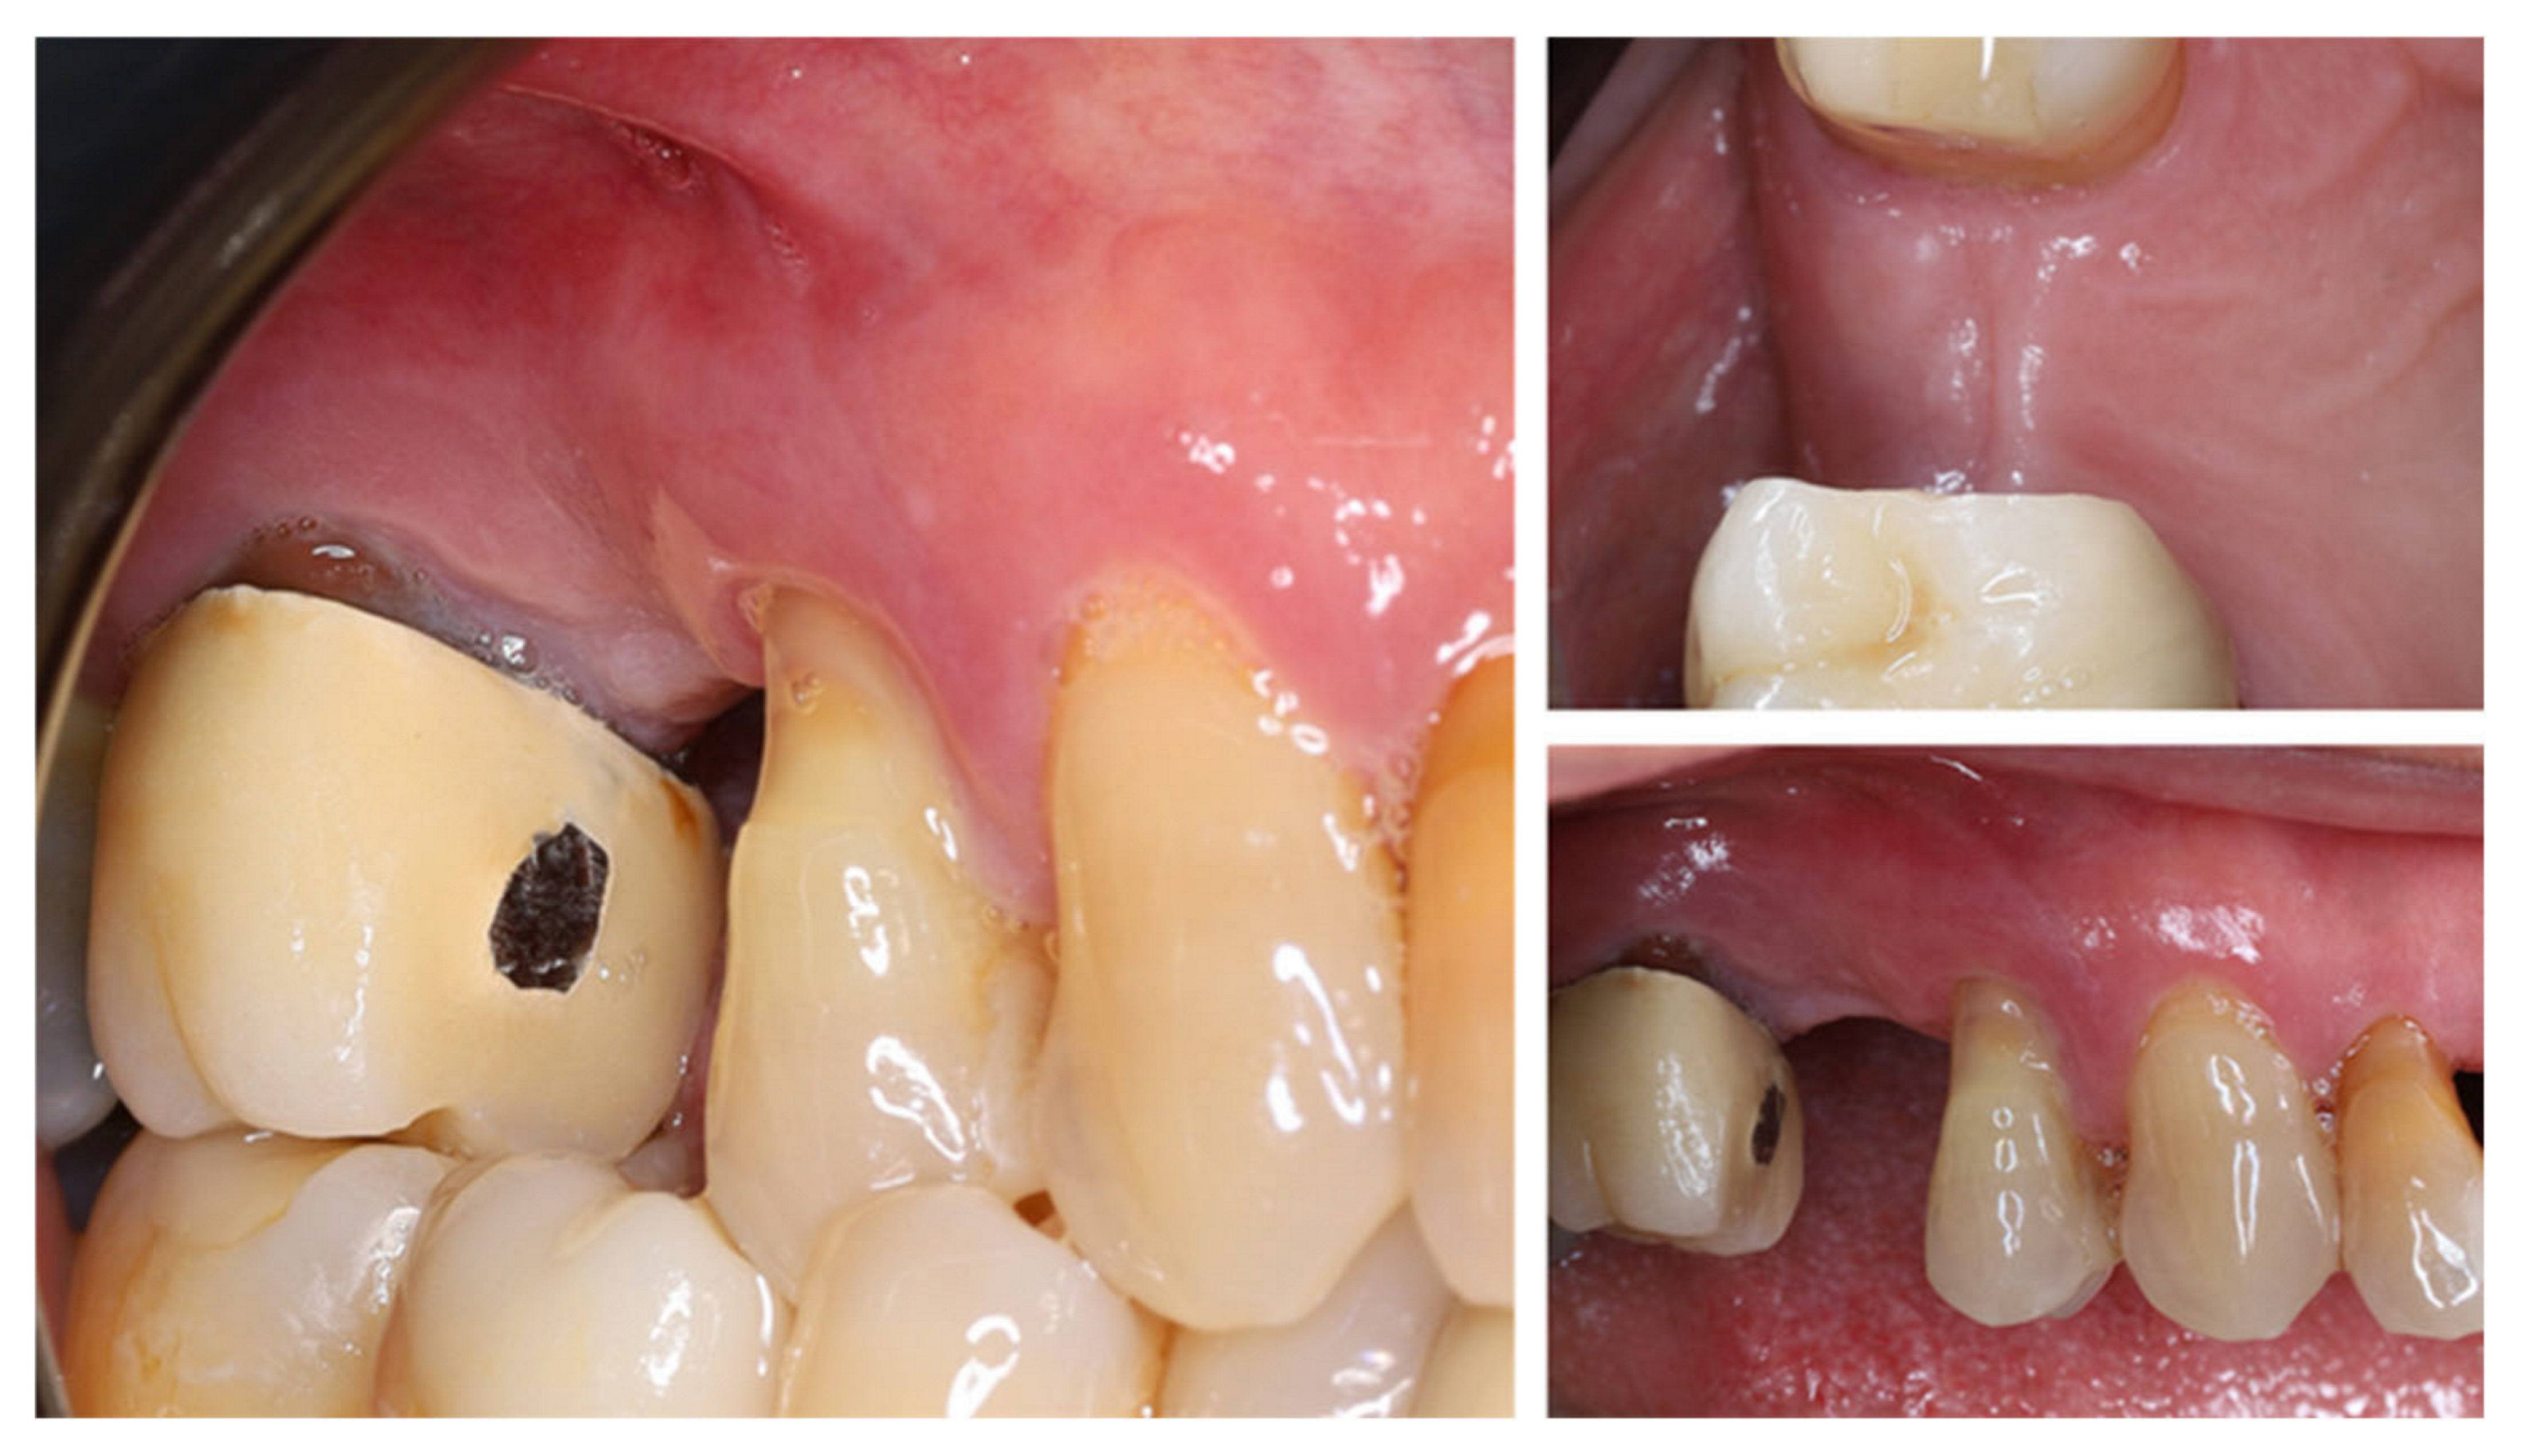

2. Materials and Methods—Clinical Case